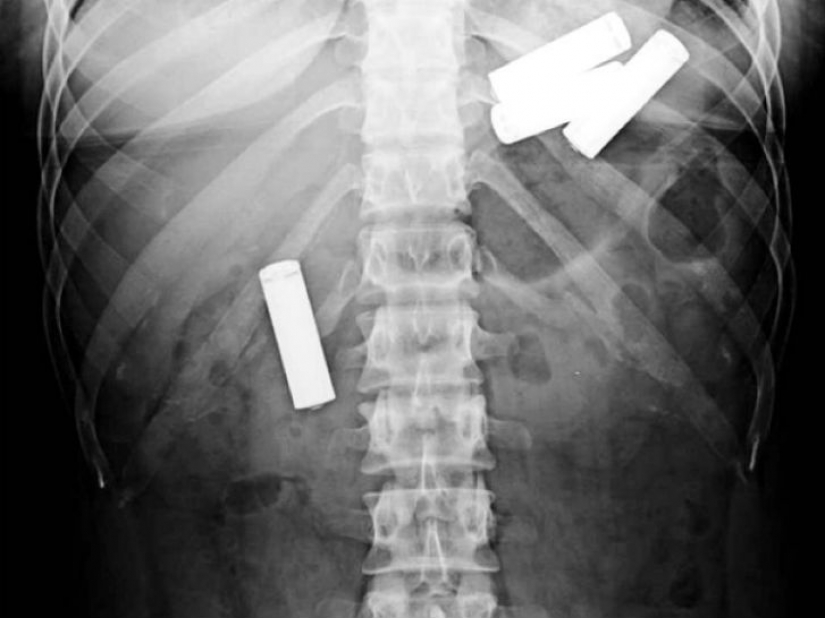

Sí, tragar la platería es caro. Cómo sobre un 78 cucharas de plata, que se tragó una de 52 años de edad, la mujer en los países Bajos?